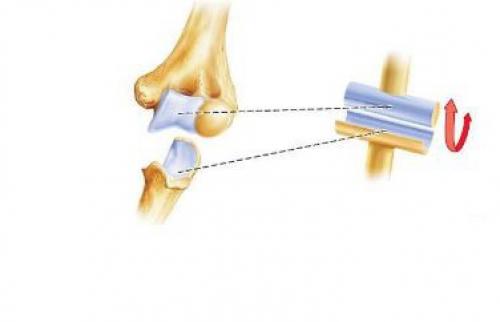

Диаграммы и схемы движения в суставах человека